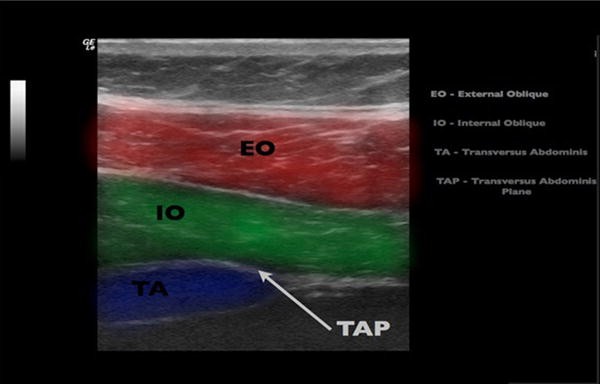

Transversus abdominis plane tap block is a technique of peripheral nerve block for abdominal anterior wall and in past years several authors demonstrated its efficacy and role in multimodal analgesia for various surgeries. The tap is a potential anatomical space between transversus abdominis and internal oblique or rectus abdominis and the field block by tap infiltration is referred to as a tap block. Block technique the aim of a tap block is to deposit local anaesthetic in the plane between the internal oblique and transversus abdominis muscles targeting the spinal nerves in this plane.

The anterior rami of spinal nerves t7 l1 innervate. A linear transducer is placed medial to the anterior superior iliac spine. These sensory nerves are in the plane between the internal oblique and transverse abdominis muscles.

Tap block anatomy. The transversus abdominis plane tap block is a relatively new regional anesthesia technique that provides analgesia to the parietal peritoneum as well as the skin and muscles of the anterior abdominal wall. The point of entry is the lumbar triangle of petit. The transversus abdominis plane tap block was first described as a landmark guided technique involving needle insertion at the triangle of petit.